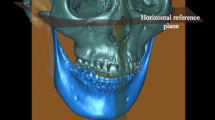

The cephalometric images were recorded using a digital CRANEX D Digital X-ray unit (73 kV, 10 mA, 17.6 s, CC-detector sensor; Soredex, Tuusula, Finland). The first author measured all images using the NemoCeph 2D software (Nemotec, Madrid, Spain). Hard tissue points were used as landmarks during cephalometric analysis, with the reference planes consisting of the Frankfort, mandibular, and cranial base planes (Table 1). Seven linear and fifteen angular parameters were used for sagittal skeletal analysis. All parameters are shown in Figs. 3 and 4.

Angular parameters used in the cephalometric analysis: (1) N–S–Ar, (2) N–A to the Frankfort plane, (3) SNA, (4) SNB, (5) SNPog, (6) N–Pog to FH, (7) ANB, (8) Ans–Pns to the mandibular plane, (9) mandibular plane to S–N, (10) mandibular plane to the Frankfort plane, (11) S–Ar–Go, (12) Ar–Go–Me, (13) N–Go–Me, (14) N–Go–Me, (15) Ar–Go to N–S